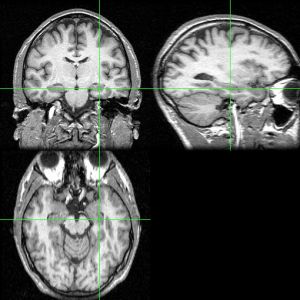

海马,是被称作“海马区”(hippocampal region)的大脑边缘系统的一部分。海马区可分为:齿状回(dentate gyrus)、海马、下托(subiculum)、前下托(presubiculum)、傍下托(parasubiculum)、内嗅皮质(entorhinal cortex)。这之中齿状回、海马、下托的细胞层为单层,合称“海马结构(hippocampal formation)”,其上下夹有低细胞密度层和无细胞层。此外的部位有复数的层面构成。齿状回与海马的单层构造对神经解剖学以及电生理学的研究进步作出了贡献。

尽管关于海马与其向邻近的大脑皮层的表述尚缺乏一致的观点,通常情况下术语上的“海马结构”指的是齿状回,CA1-CA3部位(或CA4,常称为hilus区并被认为是齿状回的一部分),以及脑下脚(另见阿蒙神之角)。CA1与CA3部位构成严格意义上的海马。